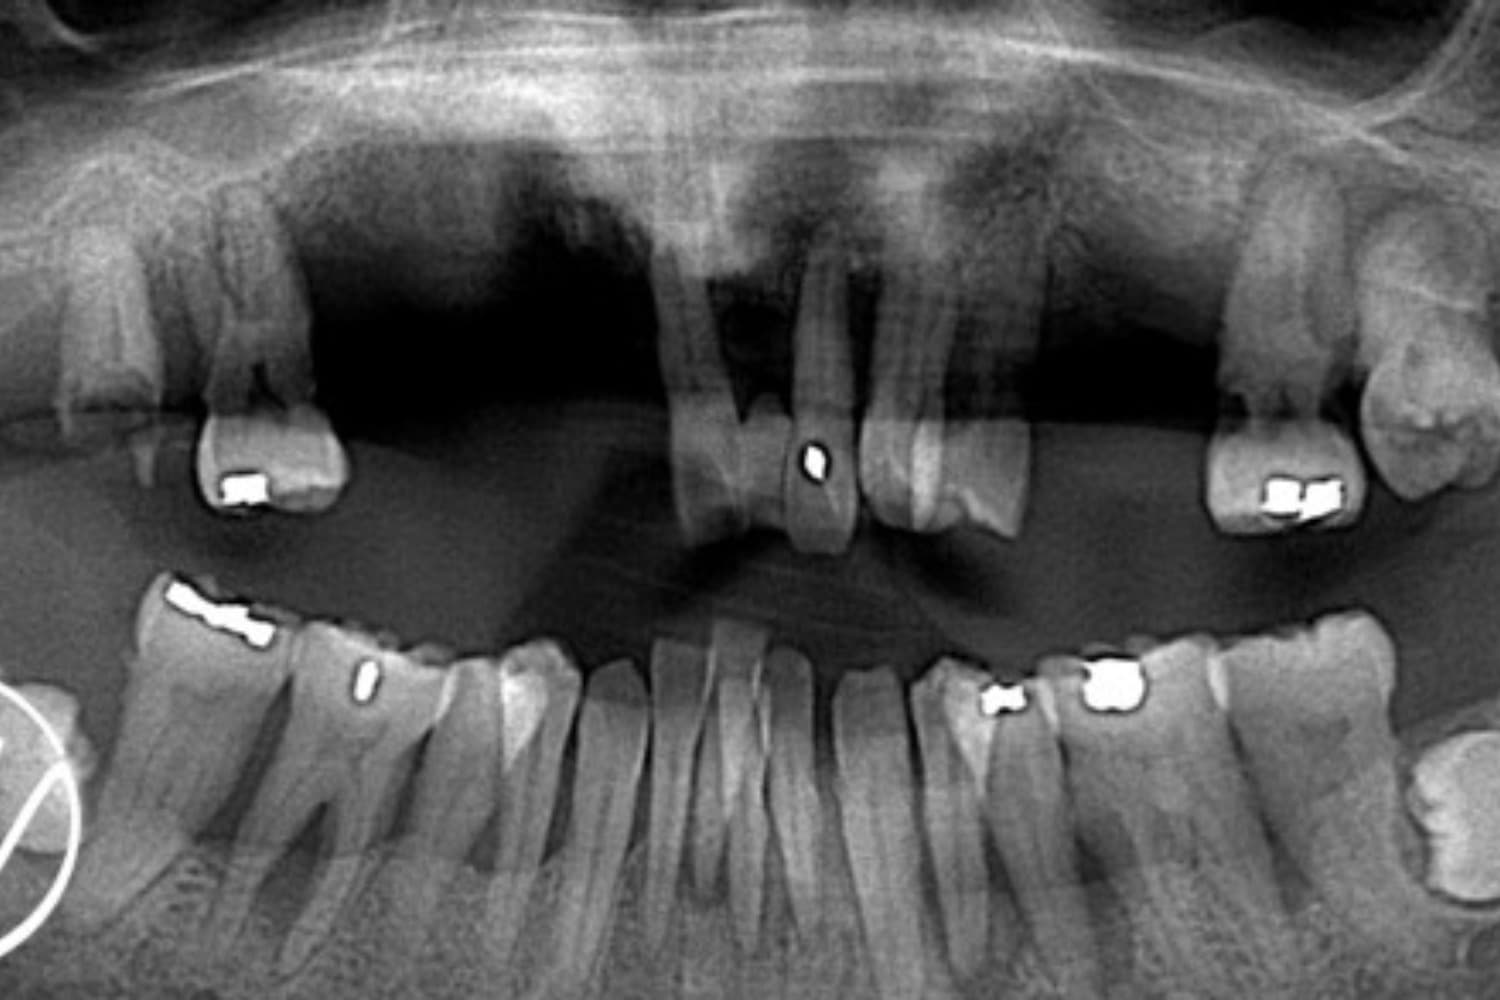

Before

下顎前歯部:抜歯後に仮歯付きブリッジを装着 上顎全体:オールオン4によるインプラント治療を選択 治療内容 治療当日に仮歯を装着し、審美性を即日回復 治療期間の短縮と出張スケジュールへの配慮 鎮静下(静脈内鎮静)でのオペによる痛み・恐怖の軽減 オペ前日 下顎前歯部を抜歯 仮歯付きのブリッジを装着。下顎前歯の突き上げを排除 オペ当日(上顎) 鎮静下にて残存歯をすべて抜歯 オールオン4の術式でインプラント4本を埋入 その日のうちに仮歯を装着し即時荷重(審美性をその日に確保)

主訴

上顎が「歯がグラグラして咬めない」「見た目も気になる」